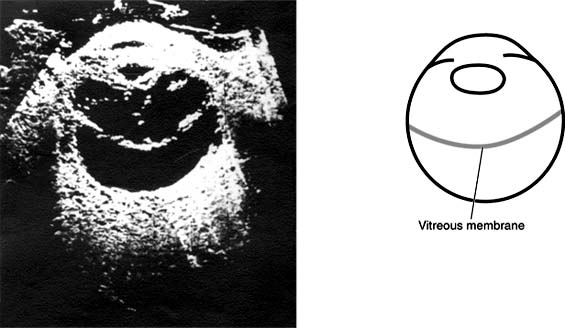

B-scan ultrasonography is an important diagnostic tool used in many posterior segment problems associated with gross vitreous opacification (Figure 9-2). Where light-dependent ophthalmoscopes and slitlamps provide insufficient information, skillful use of B-scan ultrasonography can provide much information about the vitreous and adjacent structures. For example, it is possible to identify and locate vitreous membranes (Figure 9-3), vitreoretinal relationships and retinal detachments greater than 1 mm in depth (Figures 9-3, 9-4 and 9-5), scleral ruptures, and intraocular foreign bodies (even nonlucent plastic and glass).

Figure 9-4

Figure 9-4: Vitreous membrane extending along posterior limiting membrane of vitreous from ora to ora. Retina is in place. (Reproduced, with permission, from Coleman DJ: Ultrasound in vitreous surgery. Trans Am Acad Ophthalmol Otolaryngol 1972;76:469.)

new window Figure 9-4: Vitreous membrane extending along posterior limiting membrane of vitreous from ora to ora. Retina is in place. (Reproduced, with permission, from Coleman DJ: Ultrasound in vitreous surgery. Trans Am Acad Ophthalmol Otolaryngol 1972;76:469.)